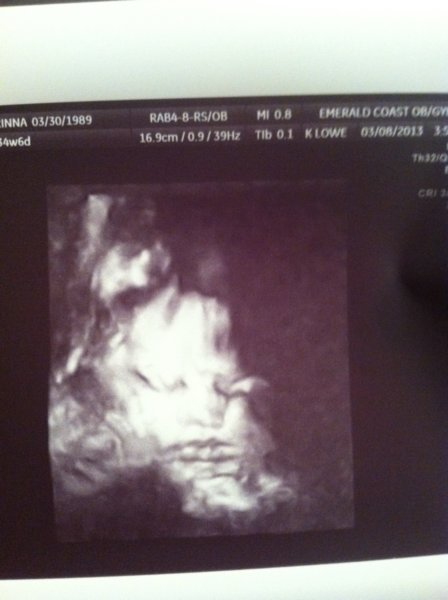

IMG_0334